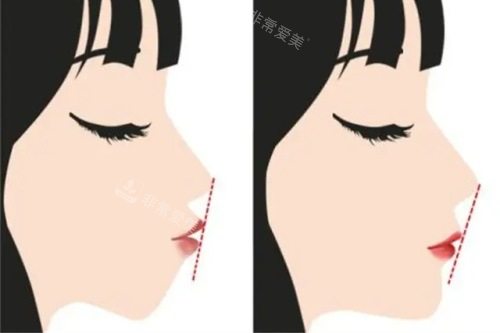

术后1个月,肿胀褪去约七成,我开始尝试软烂的食物,比如蒸蛋羹、软面包,咀嚼时的发力感和术前截然不同,以往单侧牙齿使不上力的卡顿感完全消失,只是咬合力还未完全修养好。到了术后3个月,颞下颌关节以往偶尔出现的弹响和酸胀感完全消失,日常说话、进食都改善了自然状态,只是仍需避免咀嚼坚果这类硬物。

如今距离手术已过去半年,更核心的改变是咬合功能的完全改善。术前长达数年的咬合紊乱,不仅让我咀嚼效率低下,还因长期单侧咀嚼导致咬肌不对称,这些问题如今都已不复存在。日常吃饭时,食物能被双侧牙齿均匀研磨,消化状态也比术前好了很多,再也不用因嚼不烂食物而腹胀。

面部轮廓的改变则是意料之外的惊喜。因下颌骨不对称导致的面部偏斜问题得到了精又准改善,下颌线变得流畅自然,两侧脸颊的饱满度也趋于一致,不再需要靠厚重的刘海或侧分妆容刻意遮挡。这种改变并非刻意的“整容感”,而是基于骨骼生理结构调整的自然优化,让面部比例与五官特征更契合。